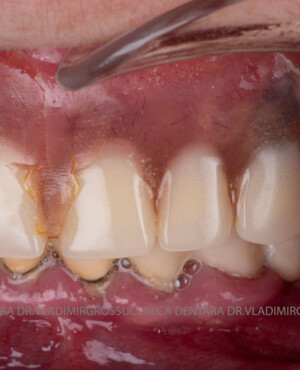

Caz 1